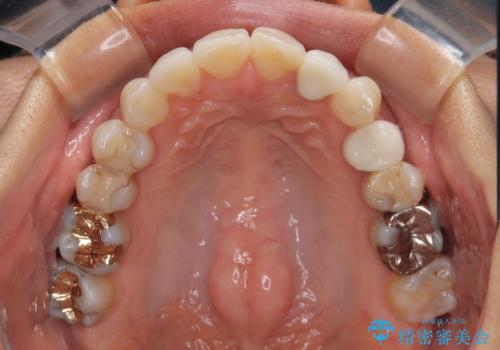

むし歯治療は、症状のある歯を矯正治療前に処置し、概ね歯列が整ったところで残りのは全て処置し、最後にインビザラインで歯列を仕上げることで、無駄なく治療を進めて行くこととしました。

しっかりと装着時間を守ってくださり、来院のタイミングに合わせてインビザラインの装着期間を調整するなど、協力いただいたおかけで、1年半の期間で全てを終えることができました。